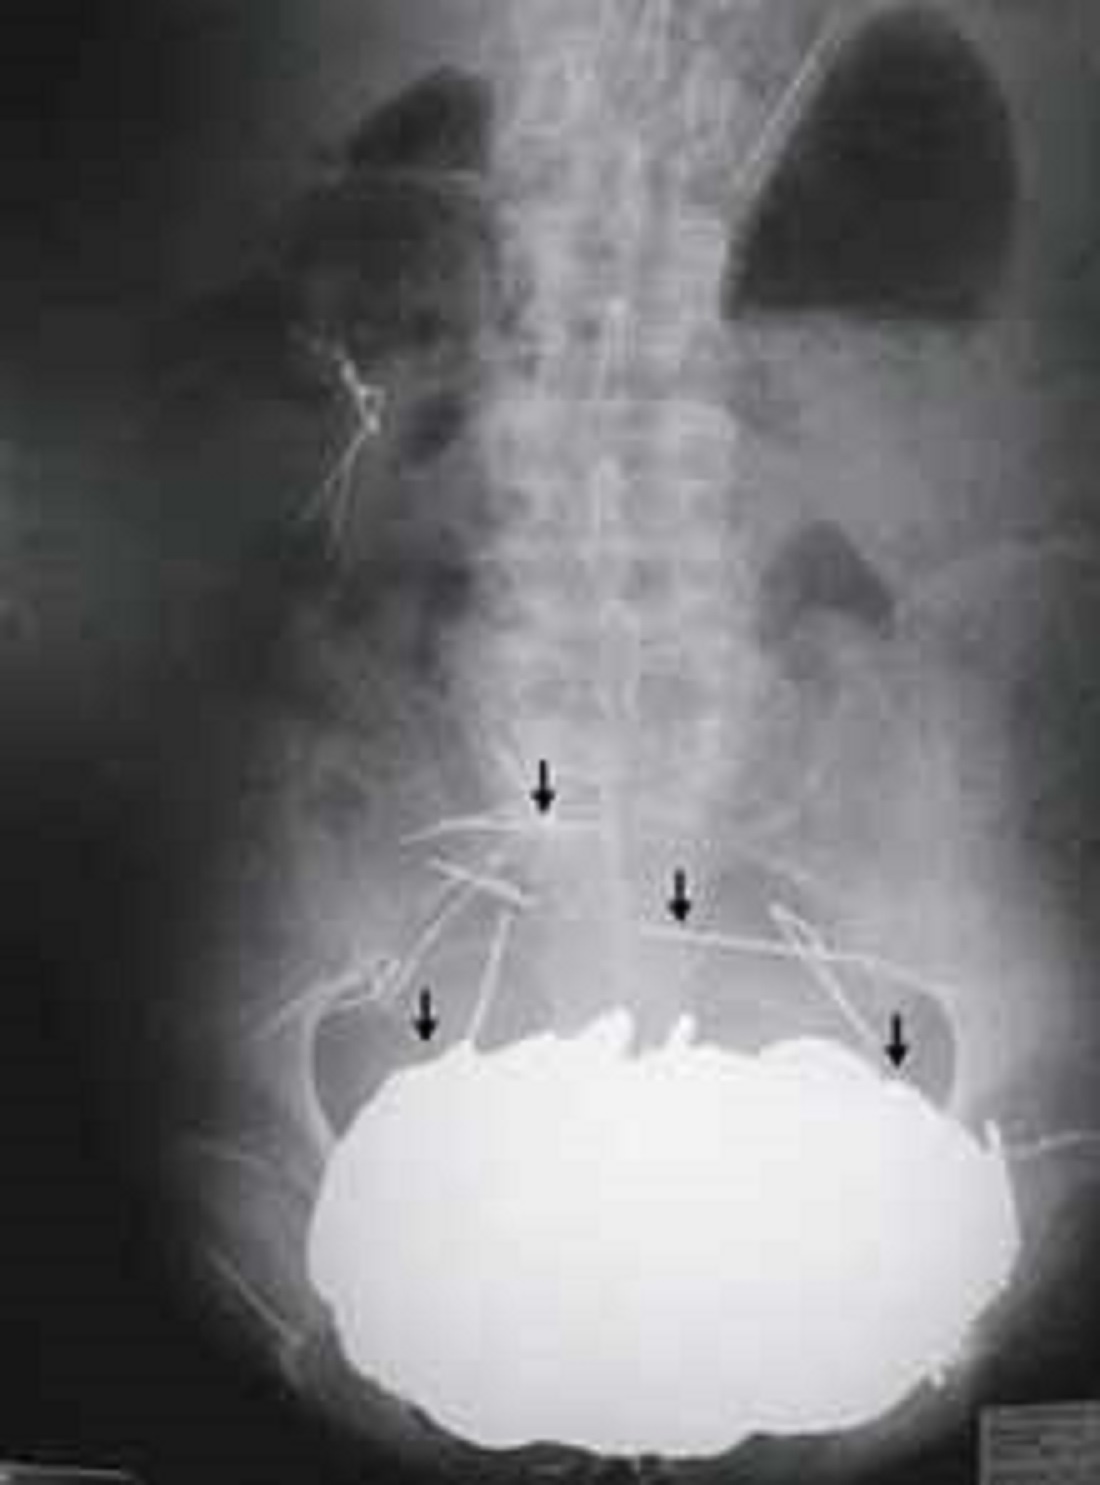

| Những vật kim loại với khối lượng gần 4,5 kg trong bụng một bệnh nhân ở Pháp. Ảnh: China Daily |

Năm 2004, một người đàn ông Pháp mắc pica, hội chứng rối loạn tâm lý ép buộc khiến ông nuốt những vật thể mà người khác không thể ăn. Trong vòng 10 năm, ông nuốt gần 4,5 kg kim loại khiến dạ dày sa xuống tận hông. Năm 2004, người đàn ông này quyết định đến bệnh viện khi các cơn đau dạ dày trở nên nghiêm trọng khiến ông không thể ăn, uống và vệ sinh, theo CBS News.

Sau khi chụp X-quang, các bác sĩ phát hiện số lượng tiền xu trị giá 605 USD, vòng cổ, kim tiêm và các vật thể khác. Mặc dù họ đã nhanh chóng lấy hết số kim loại ra khỏi dạ dày, nạn nhân vẫn chết vì các biến chứng.